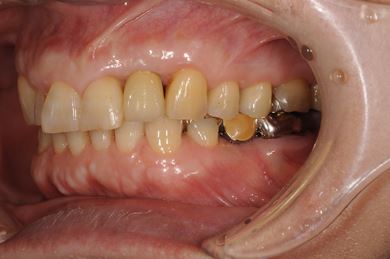

インプラントの症例写真 IMPLANT

骨再生スピードインプラント治療+セラミック治療

| 性別/年齢 | 女性 / 58歳 | ||||||||||||||||||||||||||||||||

| 主訴 | 左上前歯となりがゆらついている。他院でインプラントが必要と言われ、相談に来ました。 | ||||||||||||||||||||||||||||||||

| 治療方針 | 骨再生法によりインプラント治療を可能にする。抜歯と同時にインプラント埋入を行い、治療期間を短縮する。 | ||||||||||||||||||||||||||||||||

| 治療内容 | インプラント3本(抜歯即日スピードインプラント、GBR)、メタルボンドセラミッククラウン1本、ハイブリッドセラミッククラウン4本(ハイブリッドセラミック用土台1本) | ||||||||||||||||||||||||||||||||

| 総治療費 | 1,655,326円 | ||||||||||||||||||||||||||||||||

| 治療期間 | 1年3ヶ月 |